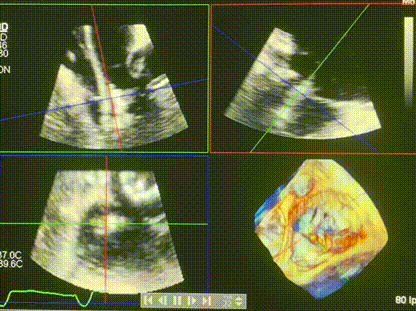

術(shù)中輸送器在超聲引導(dǎo)下調(diào)整位置

手術(shù)在全麻狀態(tài)下進(jìn)行。術(shù)者采用經(jīng)右側(cè)頸靜脈入路的方式將輸送器送入患者心臟內(nèi),在TEE及DSA引導(dǎo)下調(diào)整輸送器頭端角度,使得輸送器與三尖瓣瓣環(huán)平面垂直。在輸送器進(jìn)入右心室后釋放室間隔錨定裝置,而后釋放瓣葉夾持件(2個(gè)耳片結(jié)構(gòu))成垂直狀態(tài)。在TEE及DSA確定夾持件固定至三尖瓣葉根部且位于右室側(cè)后釋放人工瓣心房側(cè)盤片。隨后調(diào)整瓣膜同軸性以及室間隔錨定件位置(貼合室間隔),前推藏針管并固定,進(jìn)而釋放室間隔錨定裝置,并再次確認(rèn)瓣膜位置、穩(wěn)定性及同軸性,合攏輸送鞘后撤出輸送器,完成LuX-Valve Plus人工三尖瓣瓣膜的植入,僅殘余微量瓣周漏。且經(jīng)手術(shù)中心電生理團(tuán)隊(duì)評(píng)估,病人的起搏器和ICD功能沒(méi)有受到影響。

術(shù)后超聲顯示僅殘余微量瓣周漏